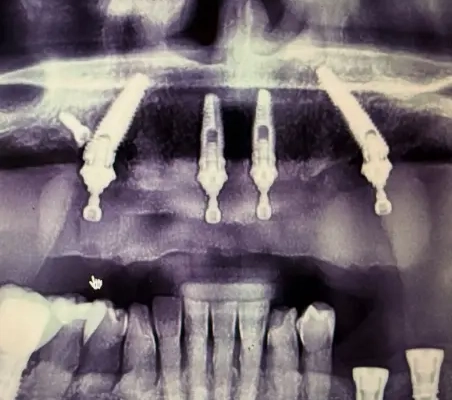

Dysfonction occlusale et esthétique avec inflammation gingivale, usure dentaire marquée et axes implantaires défavorables au maxillaire, compromettant une réhabilitation prothétique transvissée sans correction d’angulation.